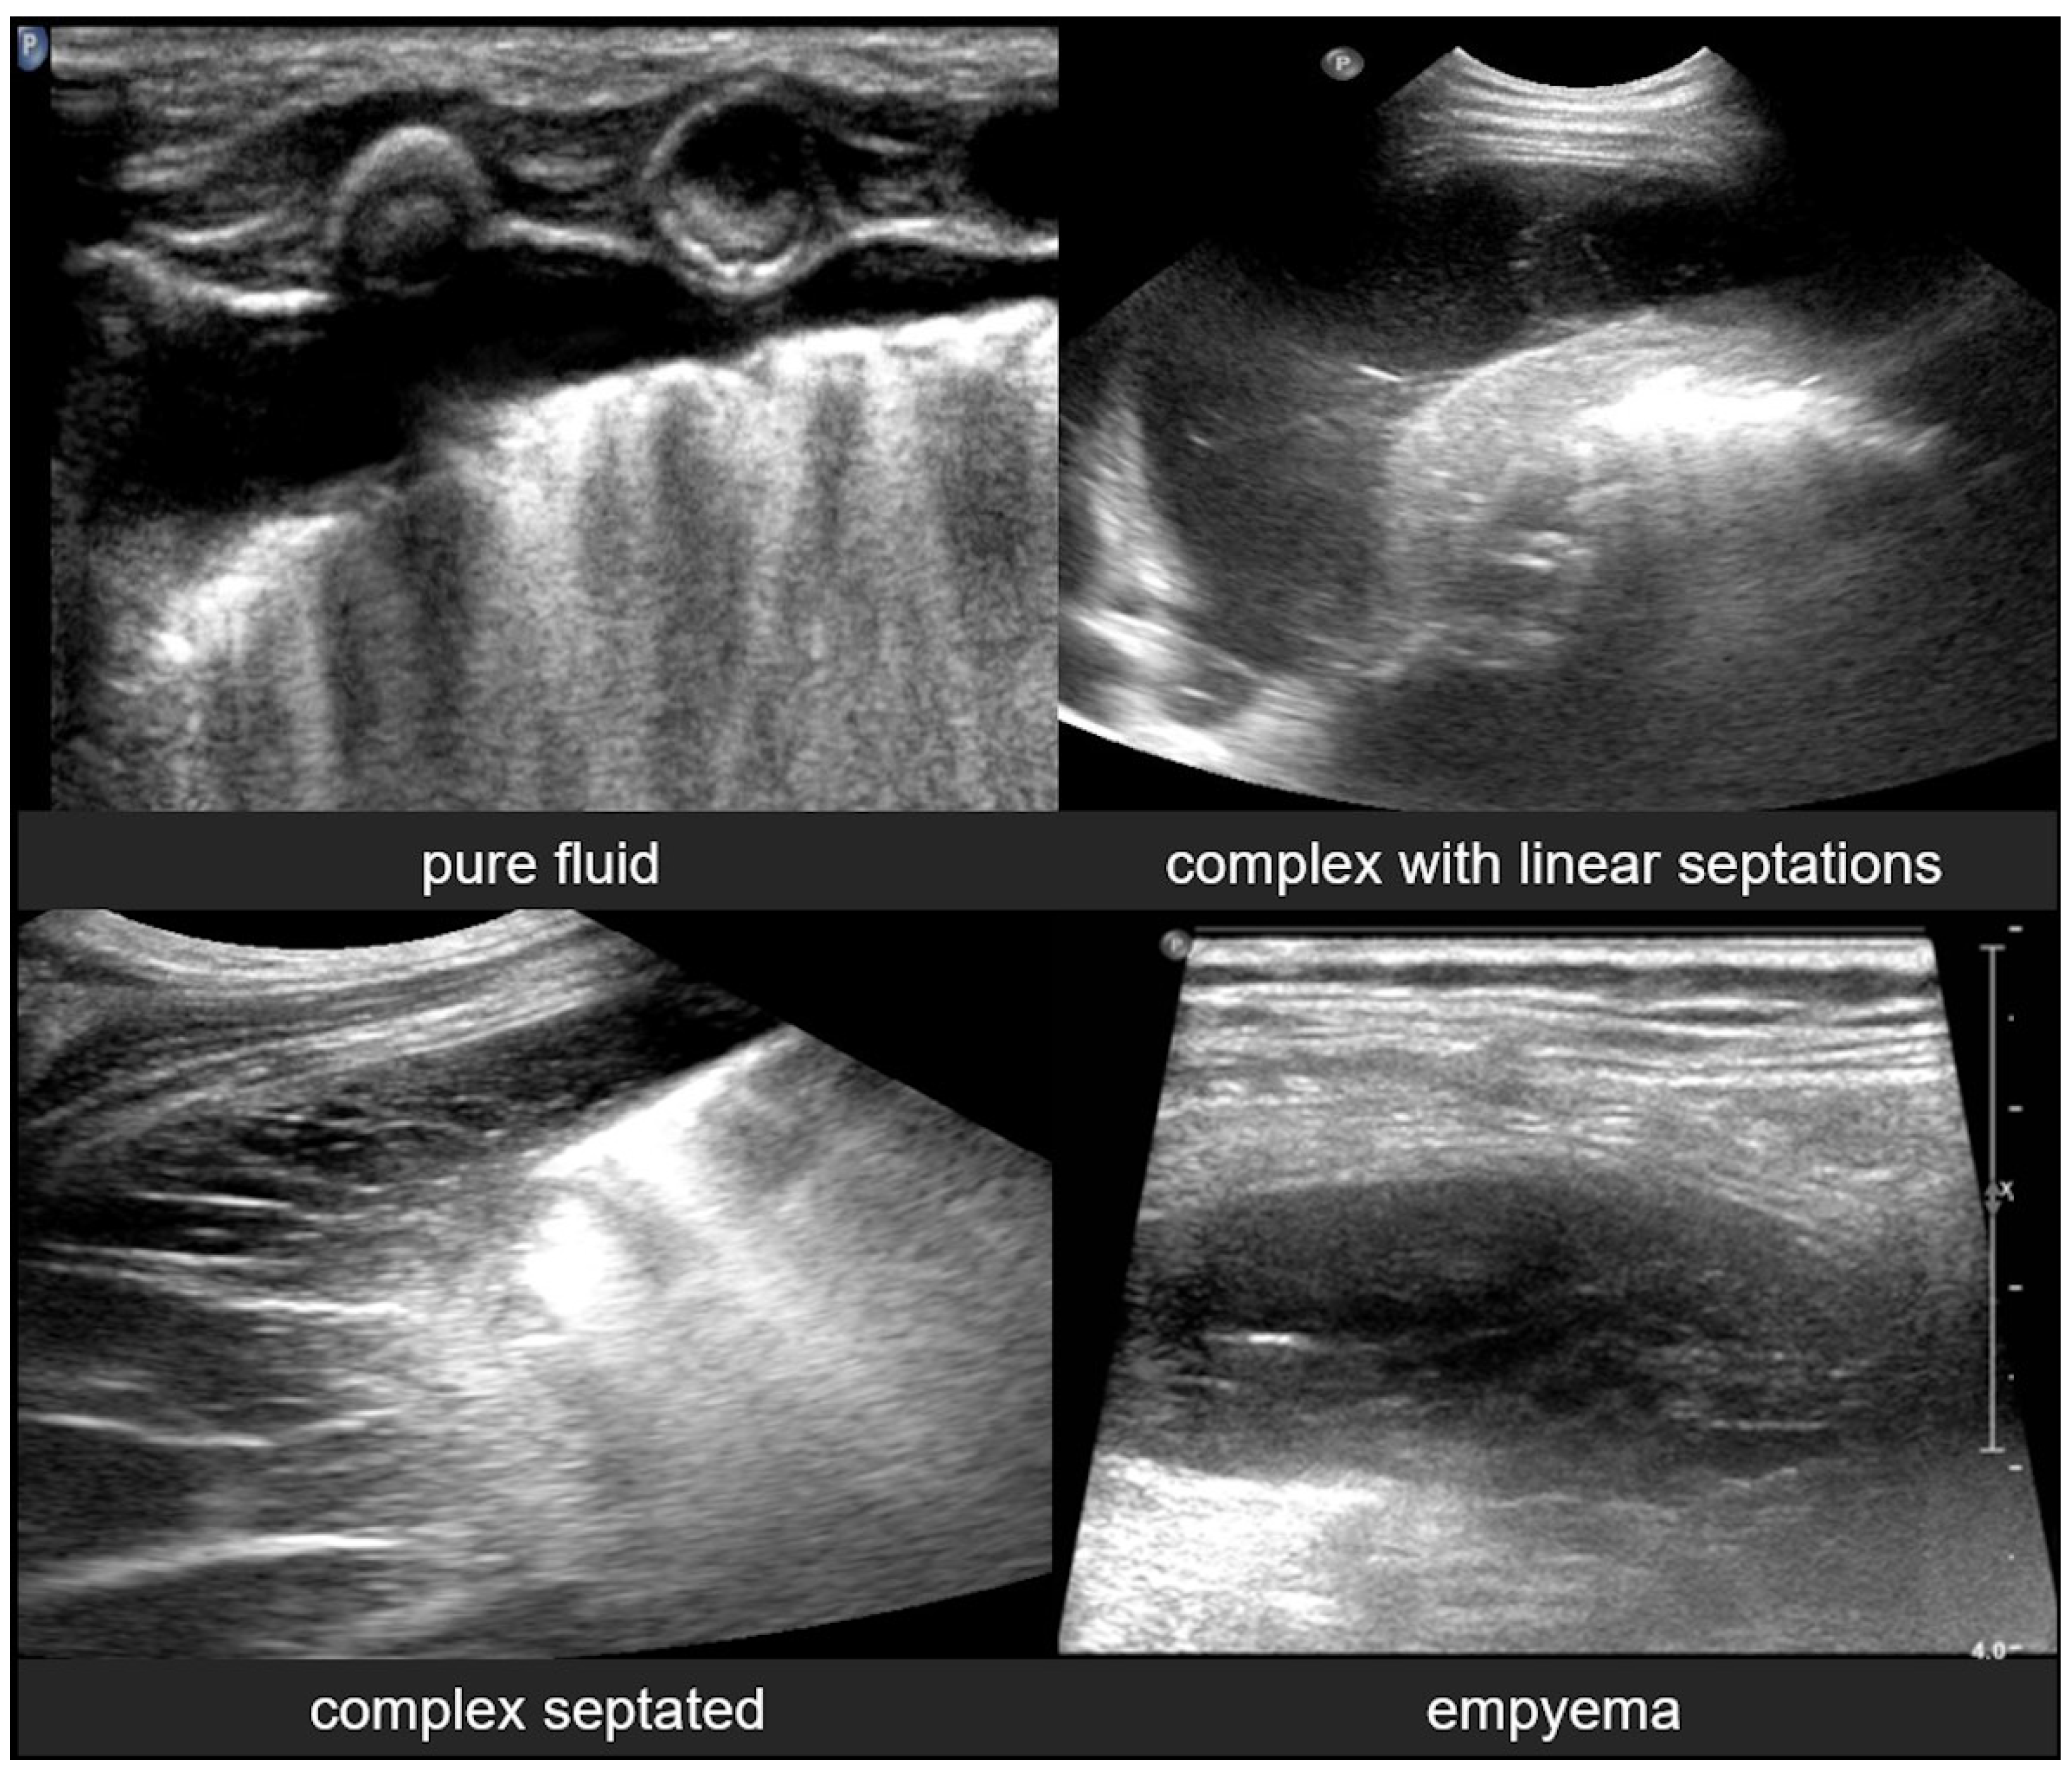

3.2.8. Pneumothorax

LUS is a highly sensitive and specific modality for the rapid bedside diagnosis of pneumothorax, particularly in critical care and neonatal settings.

The hallmark sonographic feature of pneumothorax is the absence of lung sliding, reflecting a separation between the parietal and visceral pleura due to the presence of intrapleural air. This absence is typically accompanied by the loss of B-lines, which are reverberation artifacts dependent on intact pleural contact and subpleural aeration. Instead, A-lines are observed, indicating the presence of air in the pleural space without lung parenchymal motion. When pneumothorax is evaluated in M-mode, a characteristic stratosphere sign, or “barcode sign”, replaces the normal “sea-shore sign”, showing uniform horizontal lines without the granular pattern associated with moving lung tissue. The combination of the absence of lung sliding, the absence of B-lines, the presence of prominent A-lines, and the presence of the stratosphere sign strongly supports the diagnosis of pneumothorax and helps differentiate it from other causes of respiratory distress (Figure 22) [12,13,15,20,28,29,40,53].

Figure 22.

Pneumothorax: (a) CXR, (b) LUS.